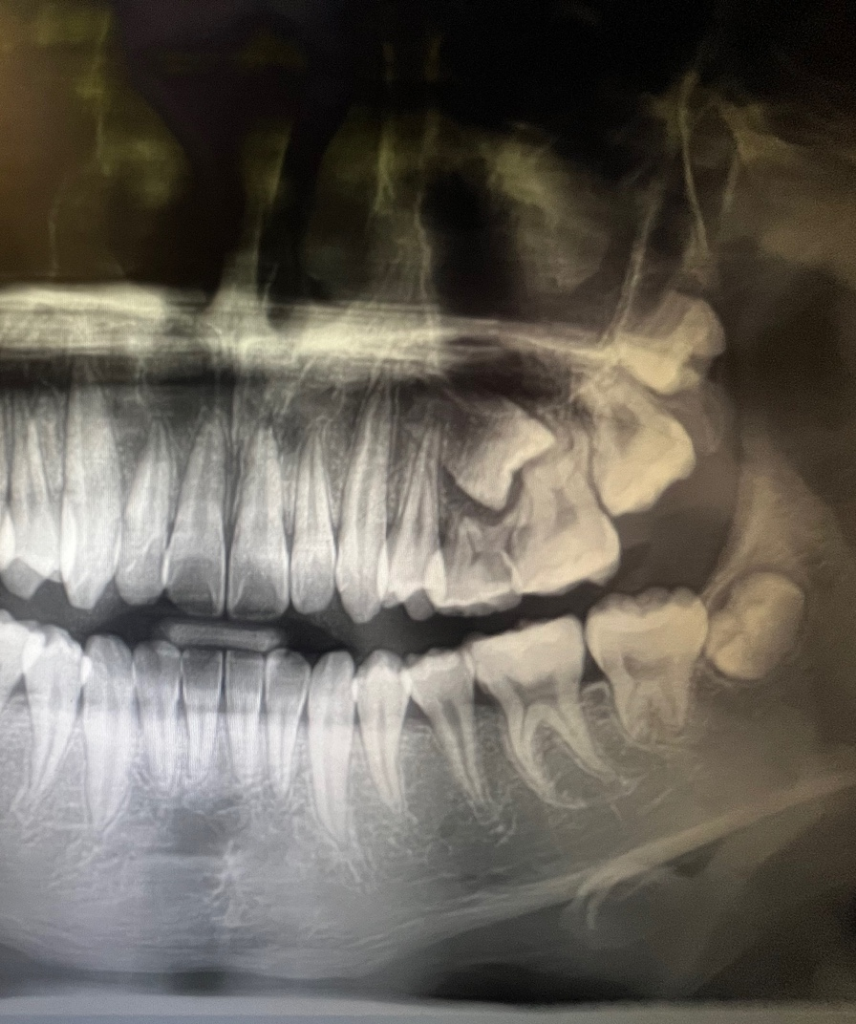

중1 아이 엑스레이 사진입니다.왼쪽 위 어금니 하나가유치가 안 빠지고 나올 영구치가 옆으로 되어있는 상태인데..상담한 결과 전체 교정하고 금액은 400전후 얘기하시는데..어금니 때문에 전체교정을 꼭 해야하나요??그 어금니 빼고는 다 괜찮대요.비용도 부담되지만 아이가 힘들어할 것도 같아서요.어금니 교정만도 가능한가요?? 그리고 발치 후 지켜보는건 안 되나요??

엑스레이 사진상으로 보면 유치를빼도 영구치가 올라오기는 힘들어 보입니다. 전체교정까지는 필요 할지는 진단을 해봐야 알겟지만, 대학병원에 가셔서 매복된 저 치아만 올릴수 잇을수도 잇으니 가셔서 검진을 받아보시는게 좋을것같습니다.